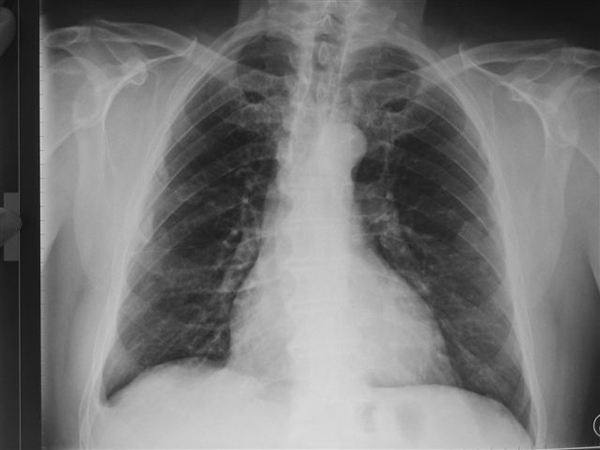

© INRS

Radiographie des poumons montrant une pathologie liée à l’amiante